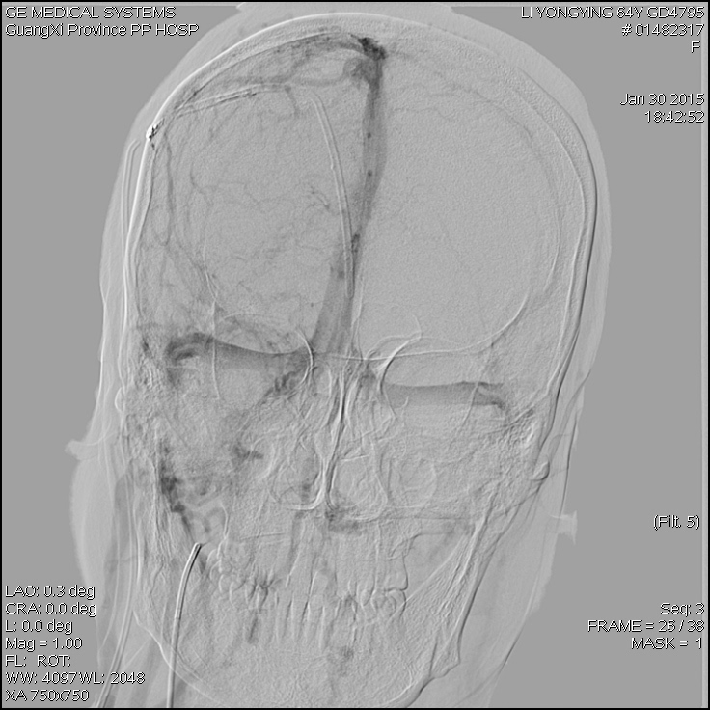

2015-1-30 DSA